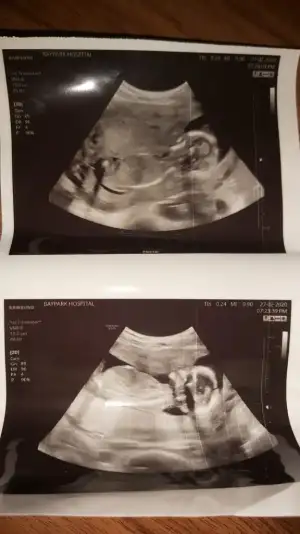

Senin nubu çizdim cnm arkadaşında çizdim pipide vardı arkadaş pipi olsa söylemezmi deyince bende diğer 10 ve 11 haftasndaki tahminim devam dedim çok istiyordu pipiyi dr görmedi deyince ne kadar geç ögrenise dedim yoksa baya baya pipiydi çizdiğim usg 😊 seninkinide çizdim parelel görünüyor tabi pozisyonu nubu bazen değiştiyor. umarım 31 yanlış tahminim var arasında olmazsın onlar beni yanıtan usgler 😊

arkadaşımın yeni usg.. 15. hafta içinde ama doktor görememiş bacakları havaya dikmiş cinsiyetini görememiş.. tahmini olan var mı? gerçi artık nuba bakılamıyor sanırım bu haftalarda.. yine de var mıdır tahmininiz 😊

Daha öncede arkadaşın usg diye paylaşmıştımız aynı arkadaşmı benim tahminim neydi 😊